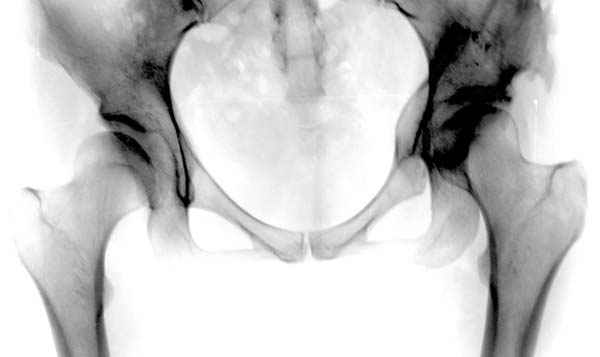

Рис.1 Трехмерная модель тазобедренного сустава с аналогом связки головки бедра. Заметно, что из торца головки выходит капроновый шнур, который с одной стороны прикрепляется к ножке бедренной части модели, а другой его конец, проходя через головку и прикрепляется к вертлужной части модели. Динамометр оказывается не нагруженным, так как аналог связки головки бедра замыкает подвижный узел модели во фронтальной плоскости.

Рис.2 Та же трехмерная модель тазобедренного сустава без аналога связки головки бедра. Пружина динамометра удерживает тазовую часть модели от опрокидывания, поддерживая стабильность так же, как отводящие мышцы обеспечивают ее в отсутствии связки головки бедра.